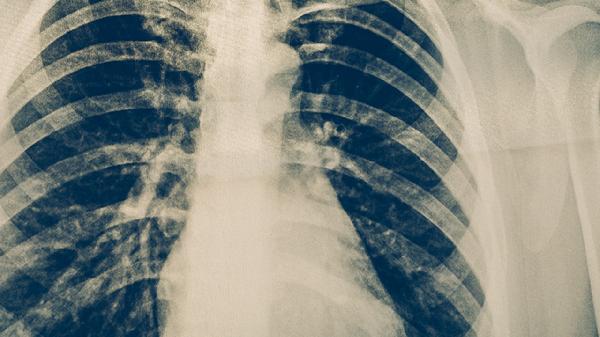

肺結(jié)核的發(fā)病因素主要有結(jié)核分枝桿菌感染、免疫力低下、密切接觸傳染源、居住環(huán)境擁擠以及合并慢性疾病等。

結(jié)核分枝桿菌是引起肺結(jié)核的主要病原體,通過(guò)空氣飛沫傳播。當(dāng)感染者咳嗽、打噴嚏或說(shuō)話(huà)時(shí),會(huì)將含有結(jié)核分枝桿菌的飛沫釋放到空氣中,他人吸入后可能被感染。感染后是否發(fā)病與個(gè)體免疫力有關(guān),免疫力較強(qiáng)的人可能不會(huì)出現(xiàn)癥狀,但免疫力低下時(shí)容易發(fā)展為活動(dòng)性肺結(jié)核。